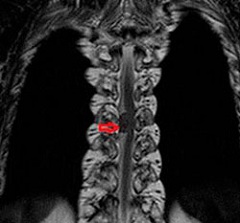

Для диагностики кисты позвоночника необходимо провести ряд исследований. Пациенту обязательно назначают магнитно-резонансную и компьютерную томографию, биопсию, ультразвуковое исследование.

Диагностика кисты позвоночника обычно начинается с медицинского осмотра и сбора анамнеза. Для подтверждения диагноза могут использоваться различные методы визуализации, такие как рентгенография, магнитно-резонансная томография (МРТ) или компьютерная томография (КТ). Эти исследования помогают определить размер, расположение и характер кисты, а также оценить ее влияние на окружающие структуры.